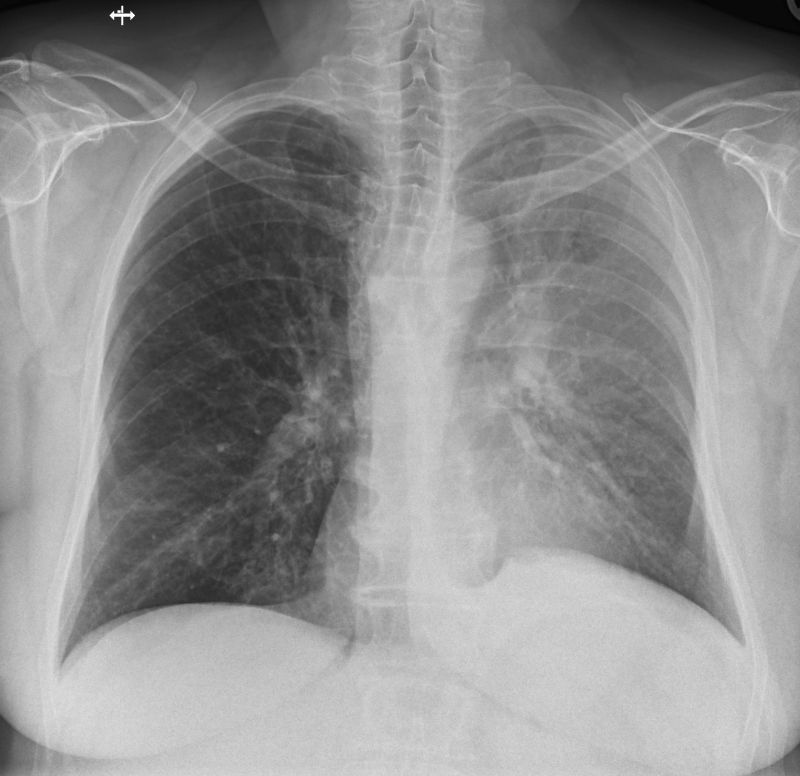

Röntgen der Lunge

Die Röntgenaufnahme der Lunge wird typischer Weise im Stehen am Wandstativ in zwei Ebenen in der Regel unter tiefer Einatmung durchgeführt. So können Veränderungen in der Lunge festgestellt und lokalisiert werden wie z.B. Tumoren, Lungenentzündung, Belüftungsprobleme von Lungenabschnitten und etliche andere Erkrankungen.